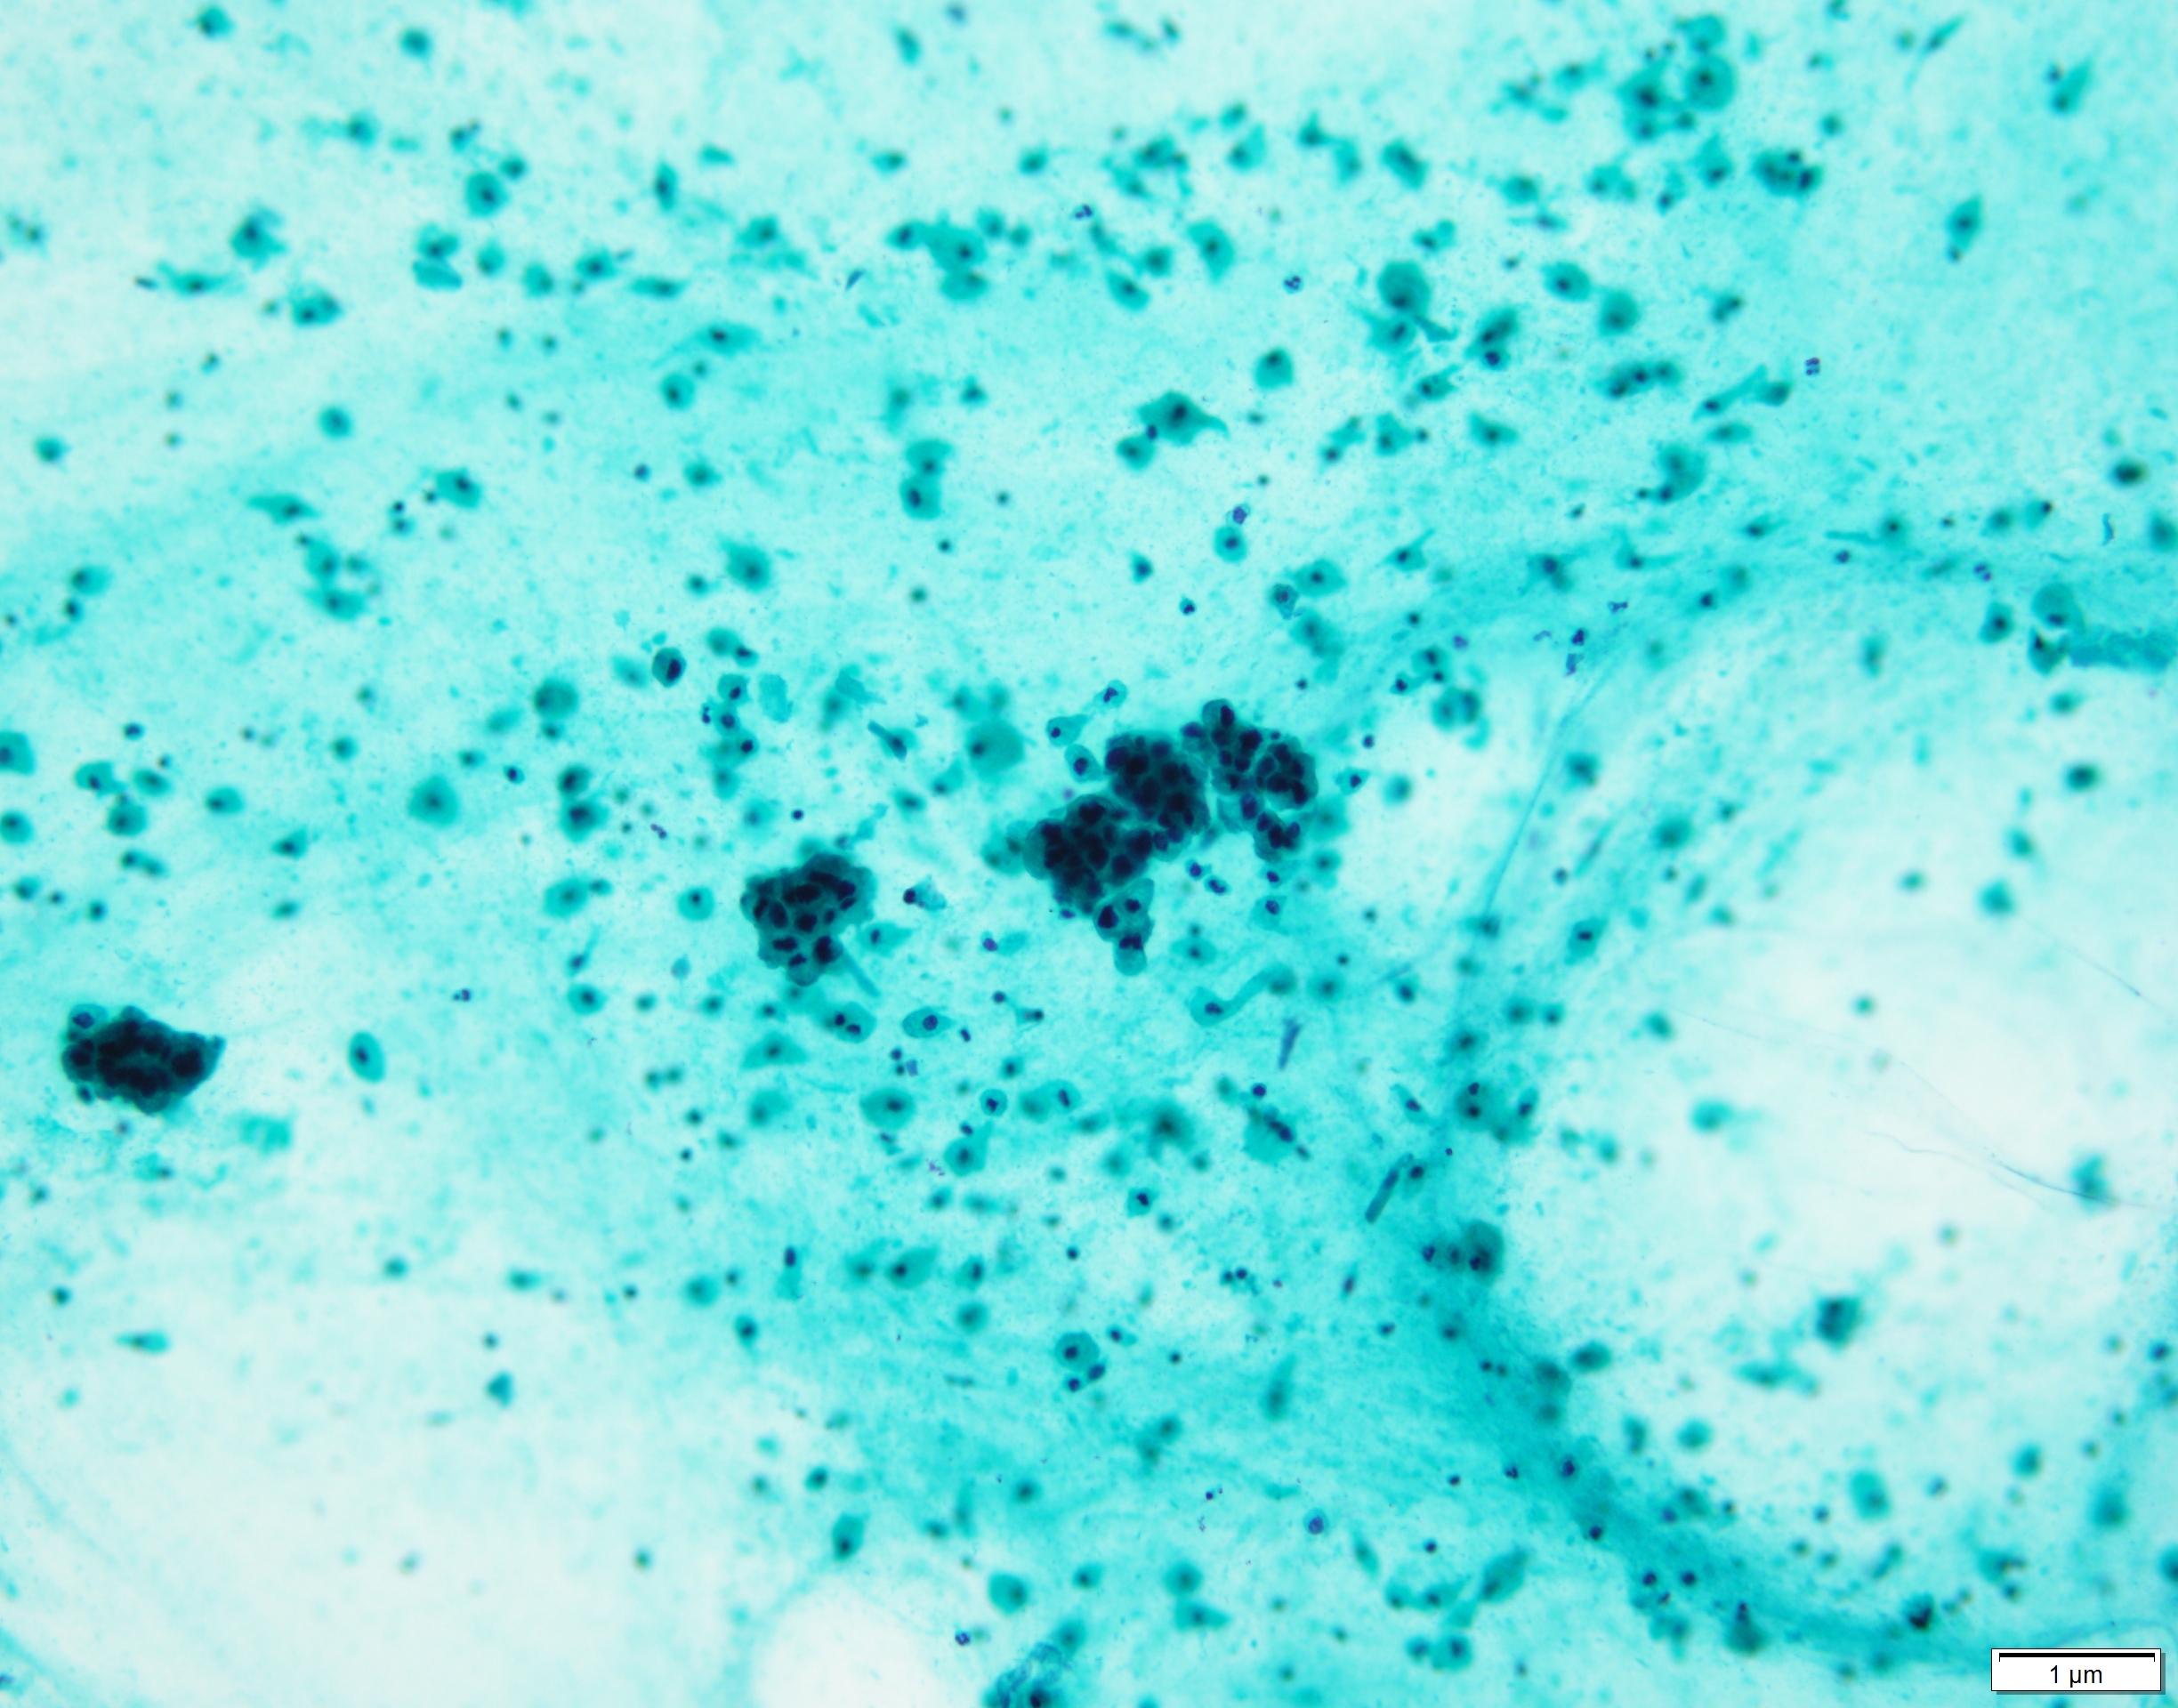

Pap×20